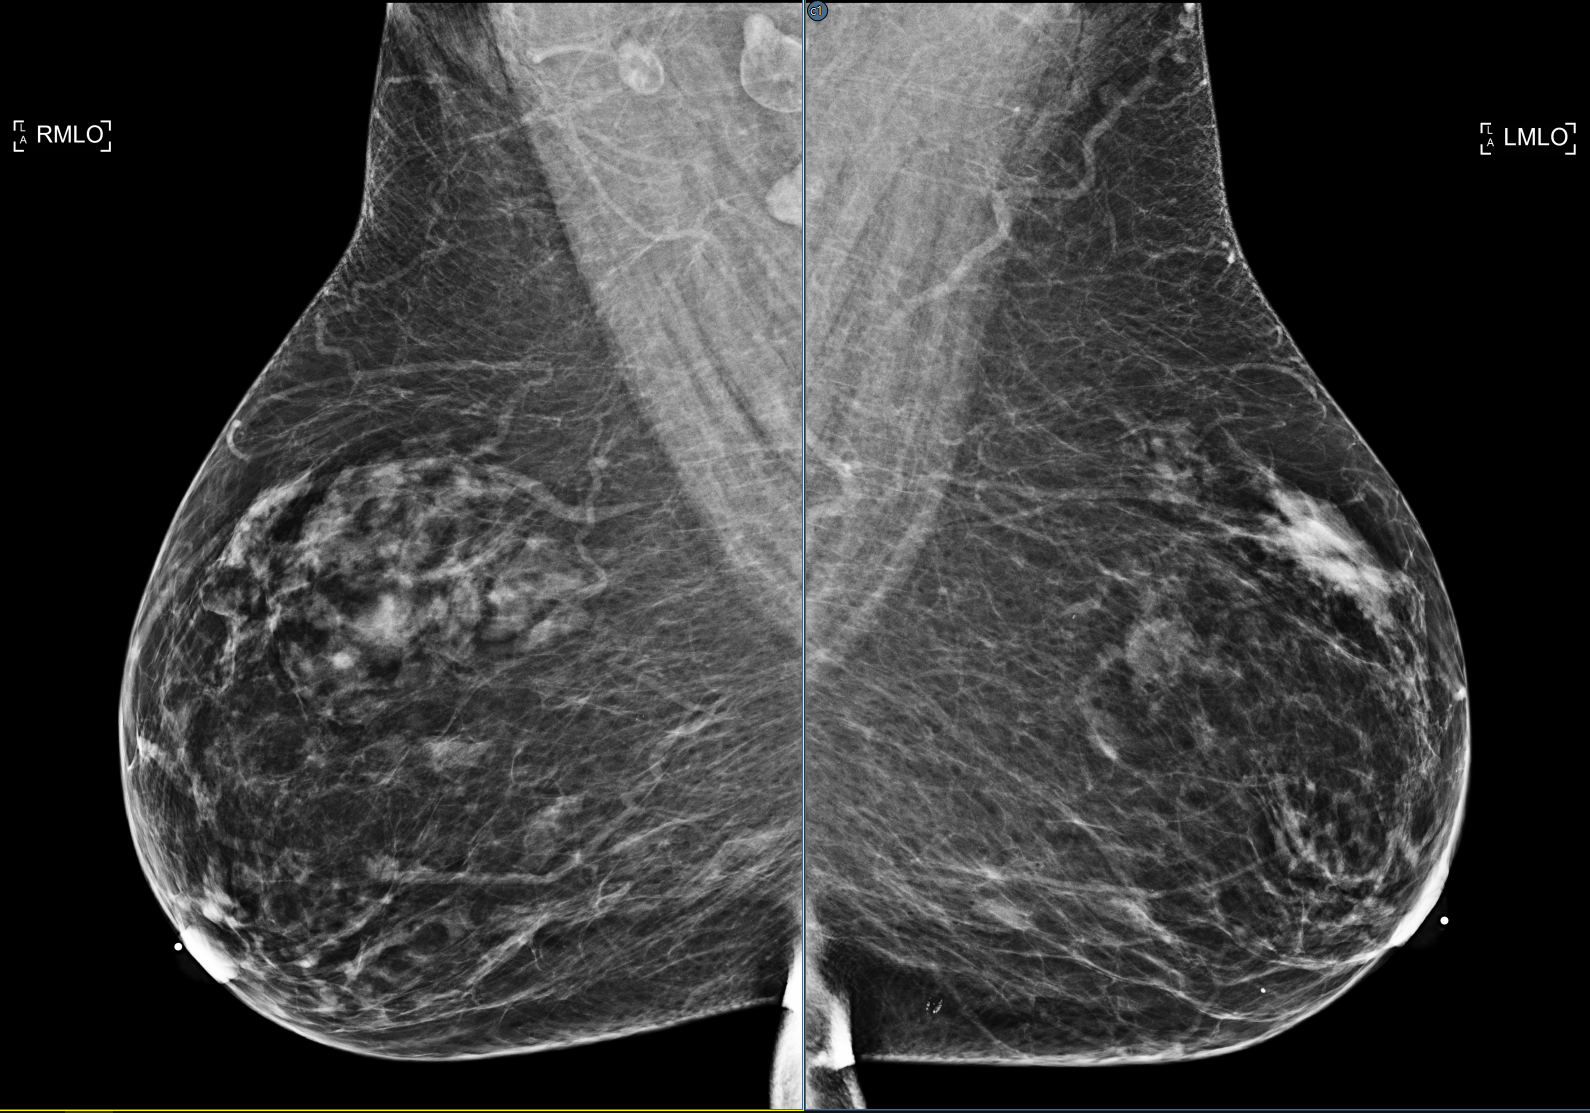

A new setting that enhances the viewer's SmartFit zoom capability by identifying anatomy that is not breast and excluding it from the normal SmartFit calculations. The data remains available by panning the image. The setting is disabled by default. The feature can be enabled from the Enhanced Smart Fit setting in the Images/Zoom section of the viewer settings panel. See Images

| Enabled | Disabled |

![]() |